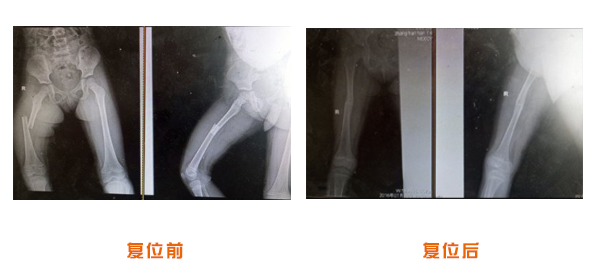

肥城市安駕莊梁氏骨科醫院是一所以梁氏手法正骨配合膏藥為特色的現代化??漆t院。

梁氏骨科術始創于清雍正年間,歷經八代,至今已有三百年歷史。據1929年泰安縣志載“梁瑞圖先生,字增生,號蓮峰,安駕莊人,精岐黃并發明接骨,凡跌打車凡跌打車軋皮不破而碎骨者......【詳細】 |